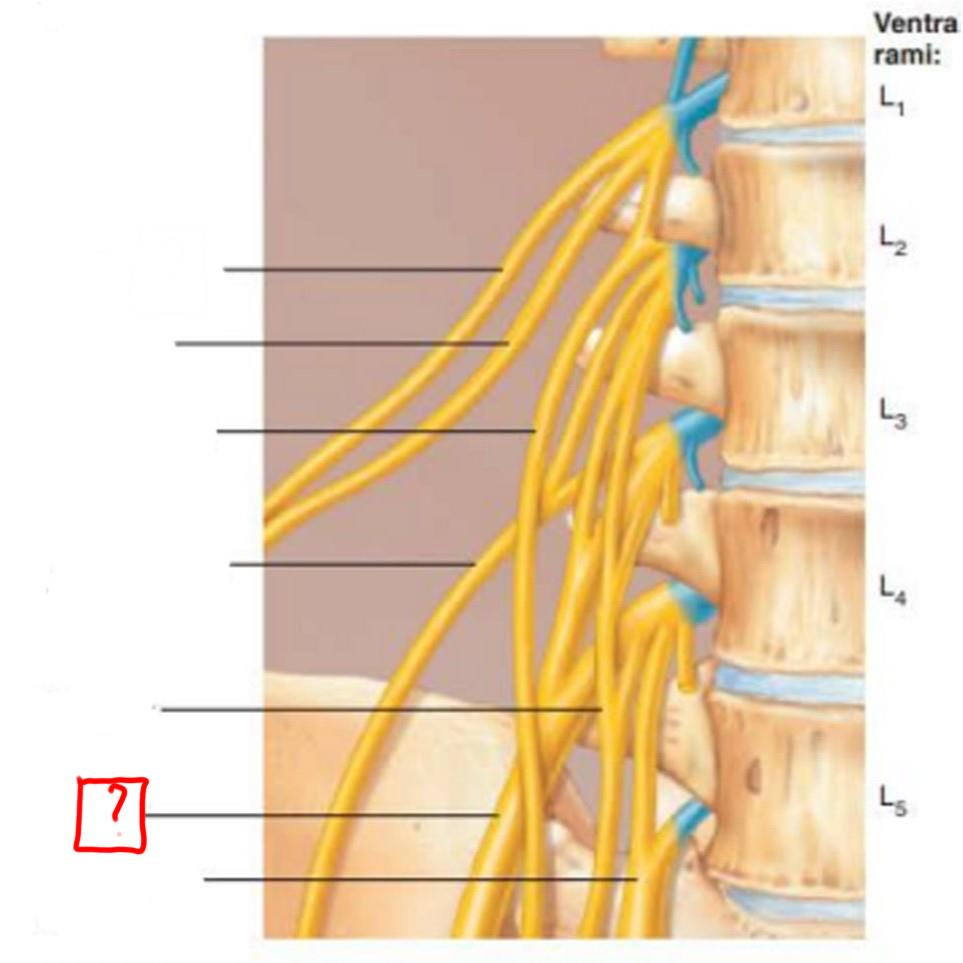

lumbar plexus

L1-L4

major nerves: ilioinguinal, obturator, femoral, genitofemoral

iliohypogastric

ilioinguinal

genitofemoral

lateral femoral cutaneous

obturator

femoral

lumbosacral trunk